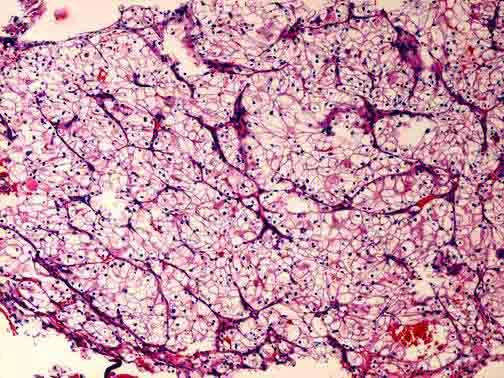

问题 男性,45岁。B超发现左肾肿物2个月。考虑为肾脏肿瘤,行左肾切除术,患肾大体如图所示,镜检如图所示,正确诊断为 ( )

选项 A.左肾透明细胞癌Ⅰ级 B.左肾细胞癌(肉瘤样型) C.左肾颗粒细胞癌 D.左肾乳头状腺癌 E.左肾梭形细胞癌

答案 A